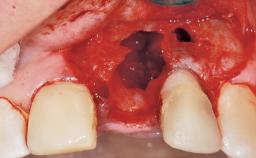

Late Flapless Placement of an Implant in a Maxillary Left Central Incisor Site

A 39-year-old male patient presented with a chief complaint of discomfort and gingival discoloration around his maxillary left central incisor. He was in good general health and was a non-smoker. His past dental history was significant because of the traumatic fracture of tooth 21 in a sporting accident at age 13. Initial dental treatment included endodontic therapy and a full-coverage restoration. The patient became symptomatic 5 years later, when structural failure of the tooth resulted in the dislodgment of the crown. Endodontic retreatment, apical surgery, and post-and-core restoration were performed.

Bone Volume Deficient horizontally, requiring prior grafting